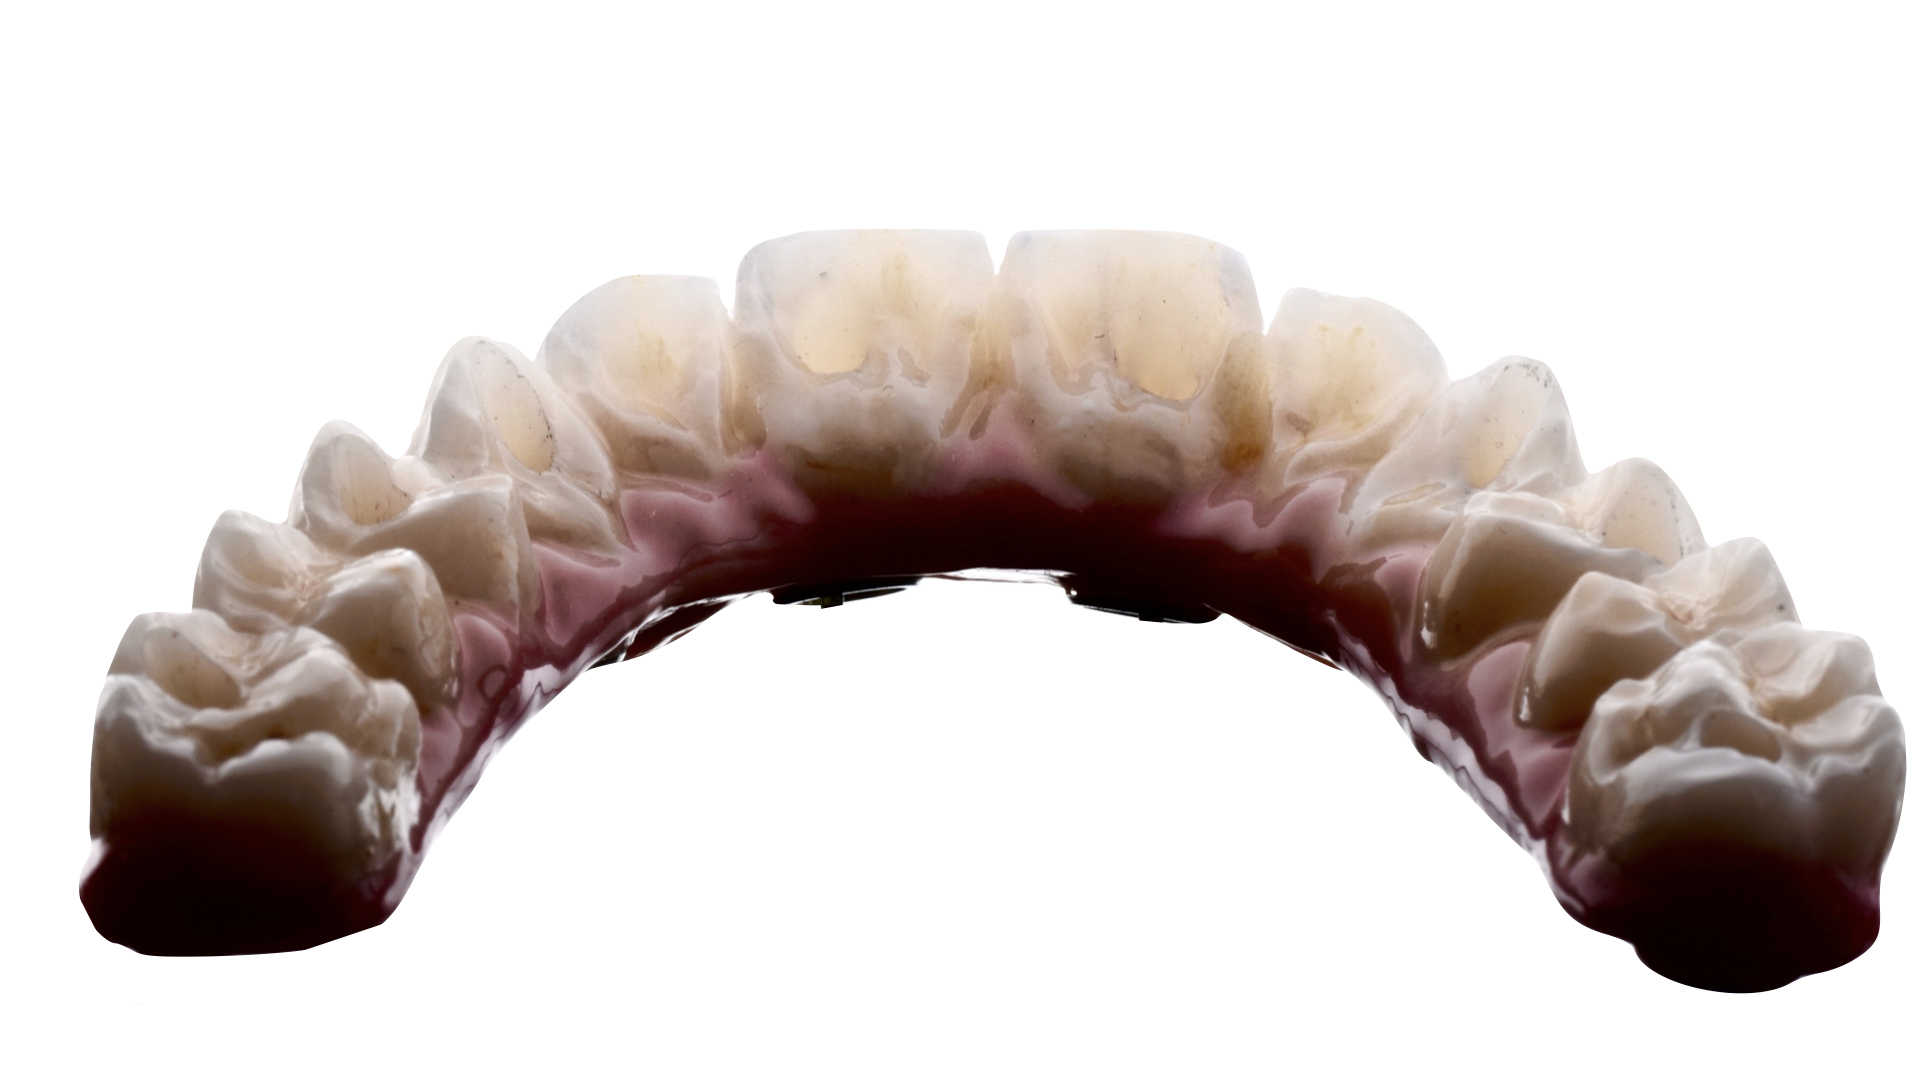

Paciente siempre había tenido mucho miedo al dentista, por lo que le propusimos proceder con la cirugía bajo sedación consciente, para que el paciente estuviera tranquilo y no recordara nada después de despertarse de la cirugía. El paciente aceptó, así que realicé la cirugía con anestesia y sedación consciente, y la cirugía salió muy bien, lo que nos permitió tomar medidas el mismo día y hacer una carga inmediata, evitando que el paciente estuviera sin dientes en ningún momento. Una vez que los implantes se habían cicatrizado, tomamos medidas para la prótesis definitiva, que en este caso fue hecha de circonio. El paciente está feliz con su sonrisa, pero sobre todo comenta que ahora puede comer con alegría.